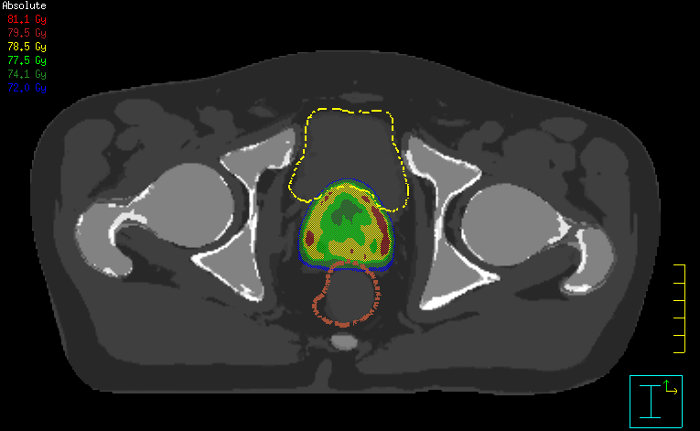

With its exceptional soft-tissue visualization capabilities and wide range of image contrasts, MRI has become a powerful tool to help more precisely define tumor boundaries. This is particularly important as it has been established that there is a high degree of uncertainty in target volume delineation, and it is even reported to represent the largest uncertainty in the entire radiotherapy process for most tumor sites**. Better visualization of the target area and nearby organs-at-risk is a key factor in enhancing target volume delineation. MRI’s expanding role also can be attributed to its functional imaging capabilities, which can inform both target characterization and treatment response.

With its superior soft tissue contrast compared to CT, MRI offers exquisite visualization of tumor boundaries and proximity to nearby critical structures.

The ability to tune contrasts can provide even more valuable information about tumor characteristics and tumor extent to facilitate enhanced delineation, and also provides possibilities for dose boosting strategies.